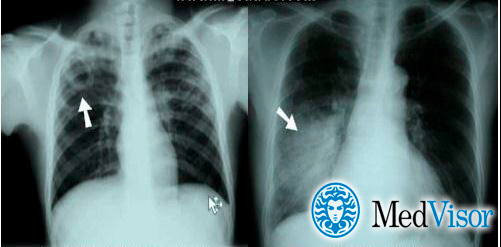

Отличия пневмонии от туберкулеза на рентгене

При пневмонии на рентгенограмме обычно видны инфильтраты и уплотнения. Типичное изображение представляет собой однородное или неоднородное белое пятно в основании пораженного легкого, либо в средней его трети. Типичным также считается плевральный выпот – скопление жидкости в плевральной полости – на той же стороне, что и очаг пневмонии.

Туберкулез обычно проявляется в виде кавитации (пустоты) в верхней части легкого. На снимке она выглядит как округлая полость. При этом также имеет место плевральный выпот.

Впрочем, отличия пневмонии от туберкулеза могут быть не такими очевидными как на снимке. Иными словами, одна флюорография не является показательной.

Рентген

Опасным воспалением при туберкулезе или пневмонии считается верхнедолевой очаг поражения, который чаще всего поражается микобактериями.

При пневмонии обнаруживаются на рентгене изменения, позволяющие отличить ее от туберкулеза:

- Уплотнение (инфильтрация) участка легких с неявными, размытыми очертаниями или в виде дымки (характерно для снимков при острой форме).

- Усиление легочного рисунка (при интерстициальной форме).

Флюорографией при пневмонии чаще выявляется поражение нижних и средних частей с изменениями корня легкого.

При туберкулезном инфицировании изменения отмечаются в верхней части легкого, отличаются четкими очертаниями, без видимых изменений корня.

На рентгенограмме обнаруживается при туберкулезе:

- Диссеминированном. Множество мелких, хорошо очерченных, или более крупных пятен, есть каверны.

- Очаговом. Уплотнение находится не ниже 2 ребра, вокруг могут быть фиброзные тяжи, усилен легочный рисунок.

- Инфильтративном. Уплотнения правильной округлой формы на рентгеновском снимке в верхней легочной доле.

- Казеозной пневмонии. Множество полостей распада с неровными краями, очагами отсева, смещением средостения в больную сторону груди.

Рентгеновские снимки на сегодняшний день являются самым надежным методом в постановке диагноза заболеваний легких. Их поражение присутствует в обоих случаях, однако картина существенно различается.

Рассмотрим основные отличия этих заболеваний на снимках:

- Локализация поражений легочной ткани. При пневмонии инфильтративные тени, характеризующие очаги поражения, просматриваются, как правило, в 3, 4, 5, 7, 8, 9 долях легкого, преимущественно поражая нижние участки. Туберкулез, в свою очередь, имеет одностороннюю локализацию, в большинстве случаев поражая правую долю легких в 1, 2, 6 сегментах.

- Очертания теней. При пневмонии инфильтраты (рентгеновские тени) имеют размытые, нечеткие очертания. В острый период заболевания затемнение напоминает дымку, а по мере развития воспаления интенсивность теней возрастает, но нечеткий характер краев сохраняется. Туберкулез же имеет тени с выраженным четким рисунком.